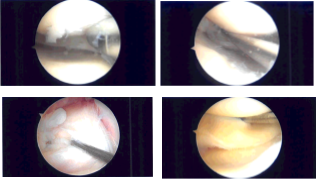

The patient was brought to the operating room where general anesthesia was induced. The right knee was prepped and draped aseptically in the usual fashion. Preoperative antibiotic was given. Lateral entry portal was made. Lateral parapatellar incision was made. Arthroscope was inserted.

The arthroscope was moved to the medial tibial femoral compartment where a medial entry portal was made with the use of a spinal needle. Examination of the medial tibiofemoral compartment showed radial tear along the body of the medial meniscus with ragged margins.

There was grade 1 to grade 2 osteoarthritic changes of the medial femoral condyle, which was cleaned with a shaver. The tear was not amenable to any repair. So, partial meniscectomy was performed with the use of right-sided biters, straight biter as well as shaver. Balanced margins were achieved.

Examination of the intercondylar notch showed intact, ACL with some degeneration. Examination of the lateral tibiofemoral compartment showed intact cartilage as well as meniscus. There was grade 1 to grade 2 osteoarthritic changes of the lateral femoral condyle in the region of trochlea, which was cleaned with the use of shaver.

Examination of the patellofemoral compartment showed intact Cartlidge. There was a inflamed suprapatellar plica extending from medial to lateral capsular wall. It was excised using the use of shaver. Final pictures were taken and saved.

Intraoperative Arthroscopy Images